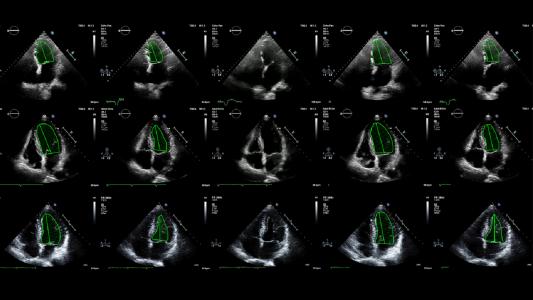

First-of-its-kind trial shows AI beat humans at analyzing heart scans

Echonet, an AI trained to assess a measure of heart function, has outperformed trained technicians in both accuracy and efficiency.